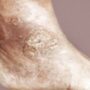

Изначально на коже больного появляются самые первые элементы в виде разных по величине папул, которые являются хроническим очагом воспаления и резко ограничены от здоровой кожи ввиду своей характерной ярко-красной окраски (лососевый цвет).

В начальной прогрессирующей фазе болезни эти папулы окружены ярким ободком гиперемии. Чуть позже папулы начинают покрываться рыхлыми серебристо-белыми чешуйками. Папулы имеют тенденцию к периферическому росту и слиянию в довольно крупные причудливой формы бляшки.

В свою очередь при слиянии бляшек могут образовываться большие очаги сплошного поражения. Количество элементов постепенно увеличивается, а в тот момент, когда их численное значение перестаёт расти, наступает 2 стадия заболевания – стационарная.